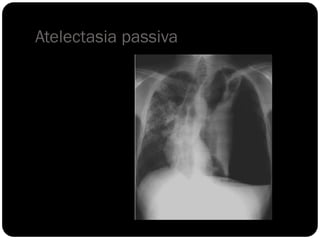

Atelectasia total

unilateral, sinal da

silhueta;

total unilateral

Atelectasia